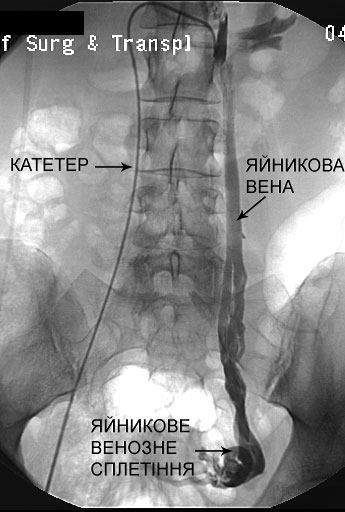

Етап 2: «Навігація» та ангіографія

Лікар-хірург під контролем рентгена обережно проводить катетер до яєчникових вен.

• Коли катетер знаходиться в потрібному місці, вводиться спеціальна контрастна речовина.

• В цей момент виконується ангіограма (флебографія) — серія знімків, на яких чітко видно розширені вени та «неправильний» рух крові.

Важливо для пацієнта: На ангіограмі до операції ми бачимо венозне «гроно», де кров застоюється. На знімку після операції ці зони зникають, оскільки кровотік там припиняється.